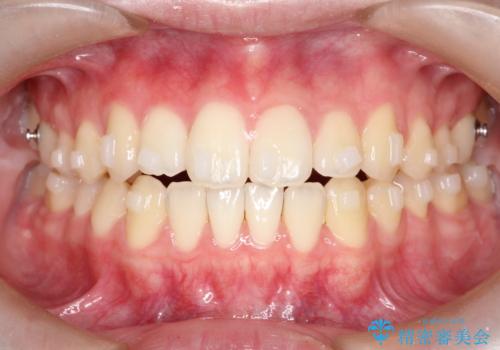

【インビザライン】前歯のガタガタをなおしたい

- 前歯のガタガタを主訴に来院されました。

開咬ぎみであったため、しっかりと前歯が噛むように計画を立てて治療をおこないました。

仕上がりも良く、患者様にも満足していただきました。

インビザラインは前歯を噛ませるような開咬の治療も得意としています。